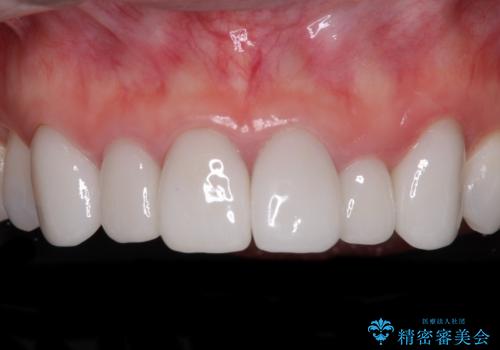

前歯は根管治療が必要となり、元々舌側に入り込んでいた左上2番目の歯は歯周外科処置により歯肉ラインを整えることとしました。

欠損部位は傾斜歯軸を起き上がらせることができたため、オールセラミッククブリッジにて補綴治療を行いました。

全顎的に満足のいく仕上がりとなりました。